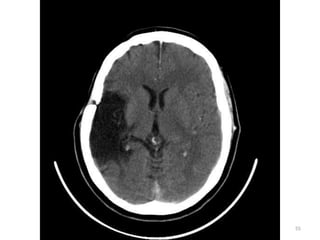

HEMATOMA INTRAPARENQUIMATOSO

• Lesões intraparenquimatosas (dentro do

cérebro) - tanto hemorragias como

contusões - acontecem dentro da

substância que faz parte do próprio

27

cérebro e não nas áreas entre o cérebro

e o crânio.

28